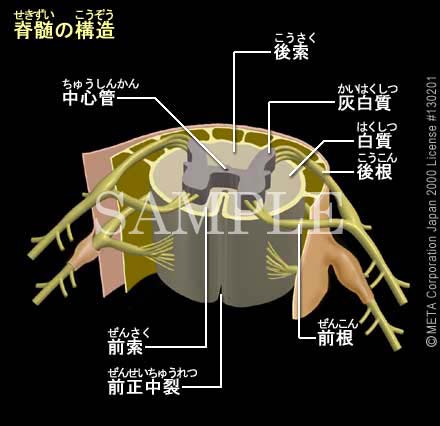

全脊椎の作用と性質

全脊椎の作用と性質